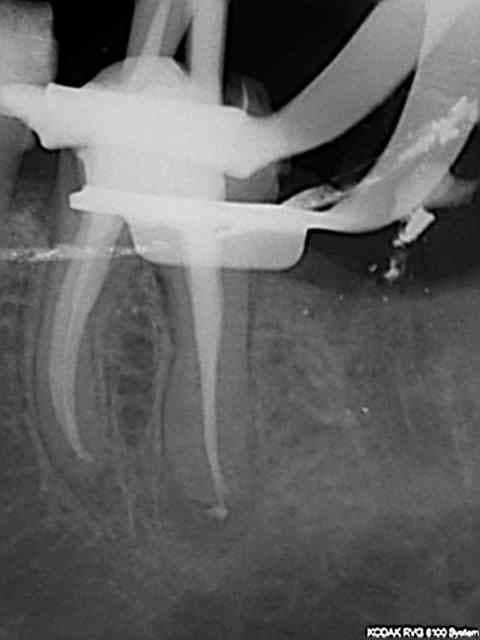

Moi c'est des radios que je vais poster et qu'on ne me dise pas que tous les dentistes se valent. C'est d'ailleurs la meme chose dans toutes les professions, faire croire l'inverse surtout en se basant uniquement sur des prix à la baisse , c'est la merde qui va monter plutôt que la qualité.

Mauvais exemple pour l'endo, c'est le meme prix, grace à qui ? C'est pas un exemple isolé , j'en ai des caisses, mais si je me met à les poster toutes ca va être lourd.